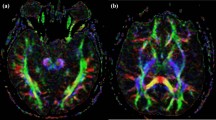

The manual volumetric measurements of the bilateral caudate nucleus and putamen were performed by using the software program AFNI (Analysis of Functional Neuroimaging) developed by the National Institutes of Health. Although AFNI was developed as a functional MRI (fMRI) tool, it also has the feature of manual volumetric measurements, which enables the simultaneous tracing of brain structures on the three planes (i.e., sagittal, axial, and coronal). Tracings were made on T1-weighted MRIs following a particular protocol for each structure (Fig. 1). AFNI calculated the volume of the structure by multiplying the pixels by the voxel volume. Each structure was traced through the slices between the first slice and the last slice where it was seen based on the medial, lateral, superior, and inferior boundaries determined for the given structure.

Caudate tracings on T1-weighted MRI images via AFNI (green area shows caudate nucleus). a Caudate tracings in the posterior coronal slices: the manual delineation of the caudate started from the very most posterior slice where it was first seen. In these posterior slices, the internal capsule (1) was the lateral and inferior boundary, the anterior (frontal) horn of the lateral ventricle (2) was the medial boundary, and the surrounding white matter was set as the superior boundary. (3) Putamen. b Caudate tracings in the slices where the nucleus accumbens was seen: in these slices, the inferior border (i.e., separation of the caudate from the nucleus accumbens) was determined by the line drawn from the most inferior point of the anterior horn of the lateral ventricle to the most inferomedial point of the internal capsule. The lower part of this line was considered nucleus accumbens and not included in the measurement. (1) Internal capsule, (2) anterior (frontal) horn of the lateral ventricle, (3) putamen, (4) nucleus accumbens. c Caudate tracings were completed in the sagittal plane

Caudate volume measurement

The coronal plane was used as the gold standard plane, although tracings were made on the three planes. Measurements started from the last slice chosen as the slice where the caudate was seen on the lateral part of the anterior horn of the lateral ventricle. The caudate was traced every other three slices until the slice where the nucleus accumbens was first seen. The internal capsule was the lateral and inferior boundary between caudate and putamen until the slice where the nucleus accumbens emerged. The anterior horn of the lateral ventricle was the medial boundary, and the white matter was the superior boundary in these slices (Fig. 1a). Starting from the slice where the nucleus accumbens was first seen, the inferior border (i.e., separation of the caudate from the nucleus accumbens) was determined by the line drawn from the most inferior point of the anterior horn of the lateral ventricle to the most inferomedial point of the internal capsule. The lower part of this line was considered nucleus accumbens and not included in the measurement (Fig. 1b). Following the coronal tracings as a guide, the tracing was completed on the sagittal plane (Fig. 1c). The axial plane was used to review and adjust the tracings where necessary.\

Putamen volume measurement

The tracings for the putamen volumetry started on the coronal plane. The first slice was the slice where the putamen was first seen as lateral and inferior to the caudate. The boundaries were as follows: medially internal capsule, laterally external capsule, superiorly, and inferiorly white matter (Fig. 2a). In the coronal slices where nucleus accumbens disappears and the globus pallidus is seen, sometimes, it becomes difficult to delineate the lateral border of the putamen. Therefore, we traced putamen every three-four slices where the lateral border was more distinct in the posterior slices. The separation of putamen from the nucleus accumbens was made the way as it was made in the caudate volumetry protocol, by a line drawn between the most inferior point of the anterior horn of the lateral ventricle and the most inferomedial point of the internal capsule (Fig. 2b). The lateral border of the putamen is particularly more distinct on the axial plane. Therefore, following the guiding tracings made on the coronal plane, the putamen was traced every other three to four slices on the axial plane (Fig. 2c). Finally, using the tracings made on the coronal and axial planes as a guide, the tracing was completed on the sagittal plane (Fig. 2d). The tracings were checked on the axial and coronal planes for the lateral border (external capsule) and medial border (globus pallidus) before the finalization of the tracing process.

Putamen tracings on T1-weighted MRI images via AFNI (green area shows caudate nucleus and orange area shows putamen). a Putamen tracings in the anterior coronal slices: the manual delineation of the putamen started from the very most anterior slice where it was first seen. In these anterior coronal slices, the internal capsule was the medial boundary; the external capsule was the lateral boundary. The superior and inferior boundaries were set as the surrounding white matter. b Putamen tracings in the posterior coronal slices: the putamen and nucleus accumbens were separated by the same way with caudate. c Putamen tracings in the axial plane: the lateral boundary of putamen is particularly more distinct in the axial plane. The coronal tracings were corrected accordingly in the axial plane. d Putamen tracings in the sagittal plane: the tracings were completed in the sagittal plane as we did for the caudate tracings